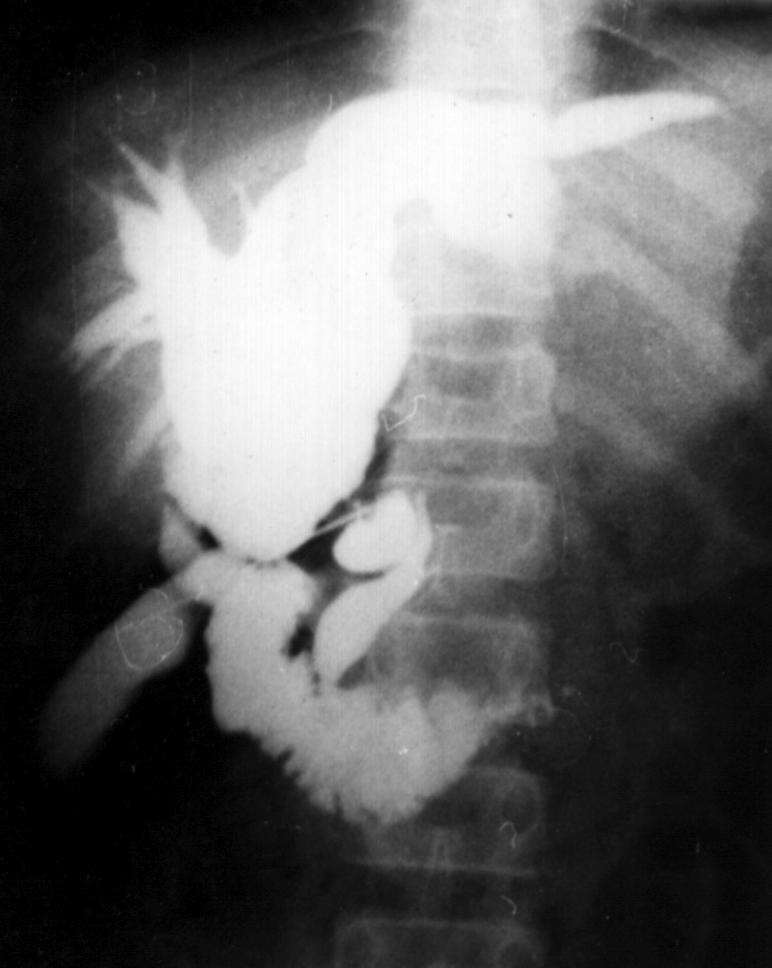

Cbd2.jpg (48471 bytes)